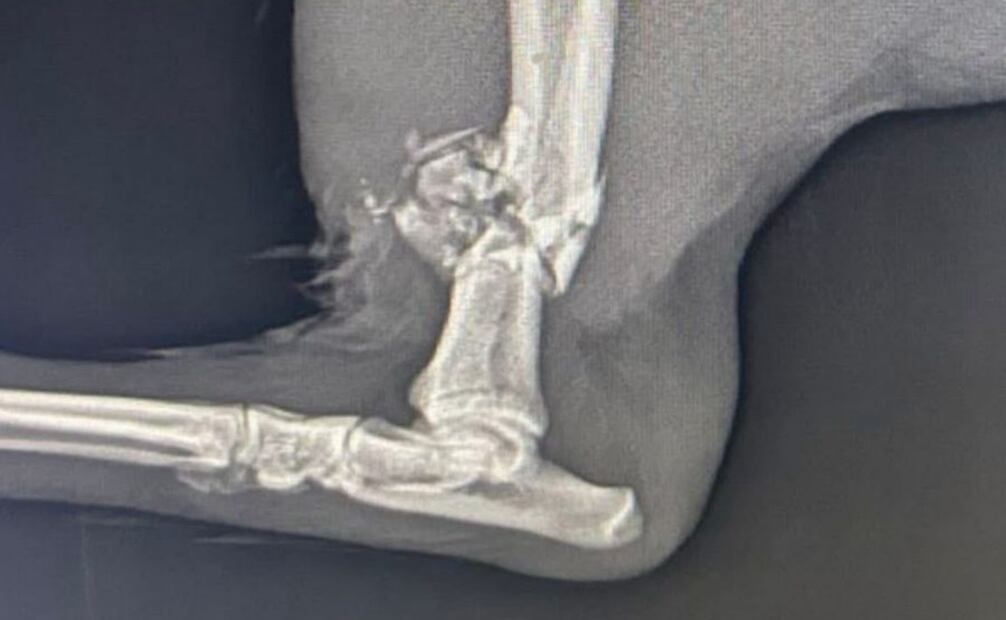

La rescatista señaló que los agentes accionaron sus armas en al menos dos ocasiones. Uno de los disparos destrozó una de las patas traseras del animal, mientras que otro impactó en el músculo.

El perrito, identificado como “Hachi”, fue localizado gravemente herido debajo de un brincolín, donde se refugió tras el ataque. Vecinos de la zona intentaron auxiliarlo, pero al no contar con los recursos necesarios, solicitaron apoyo de la ciudadanía.

Ante esta situación, la activista, quien dirige el refugio HOPEful acudió al lugar y rescató al can. Posteriormente fue canalizado a atención médica, donde se determinó que necesita una cirugía ortopédica especializada.